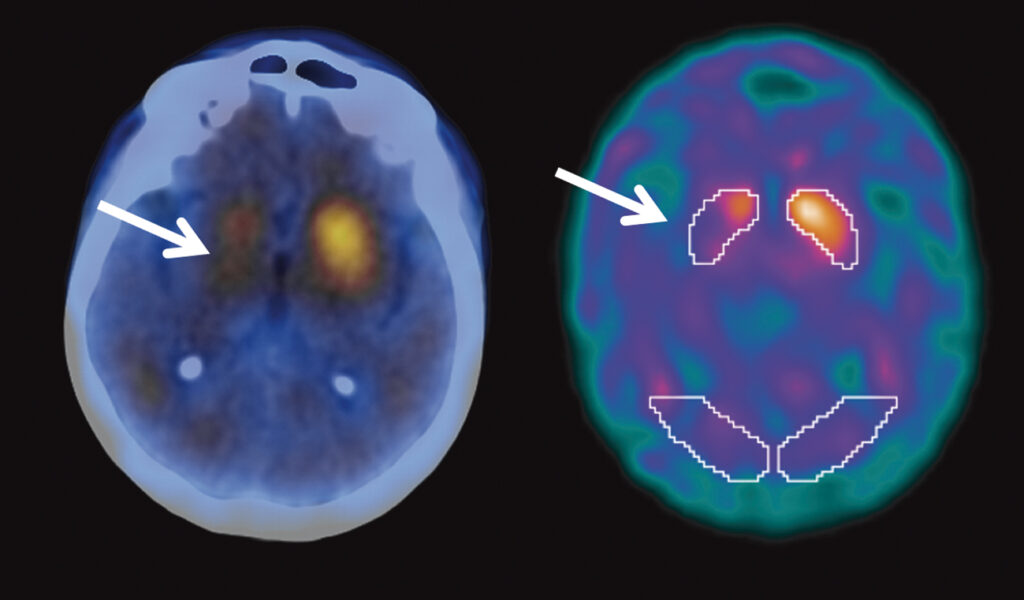

Porém, alguns exames podem ser usados para descartar outras doenças que causam tremor, lentidão ou rigidez. Os mais comuns são:

- Ressonância magnética do cérebro, que ajuda a excluir outras causas.

- SPECT cerebral com TRODAT, um exame específico que pode auxiliar em casos de dúvida, mostrando como está o funcionamento dos neurônios que produzem dopamina.

Mas é importante saber que, na maioria das vezes, o diagnóstico é feito pelo neurologista, através da análise dos sintomas e do exame físico.